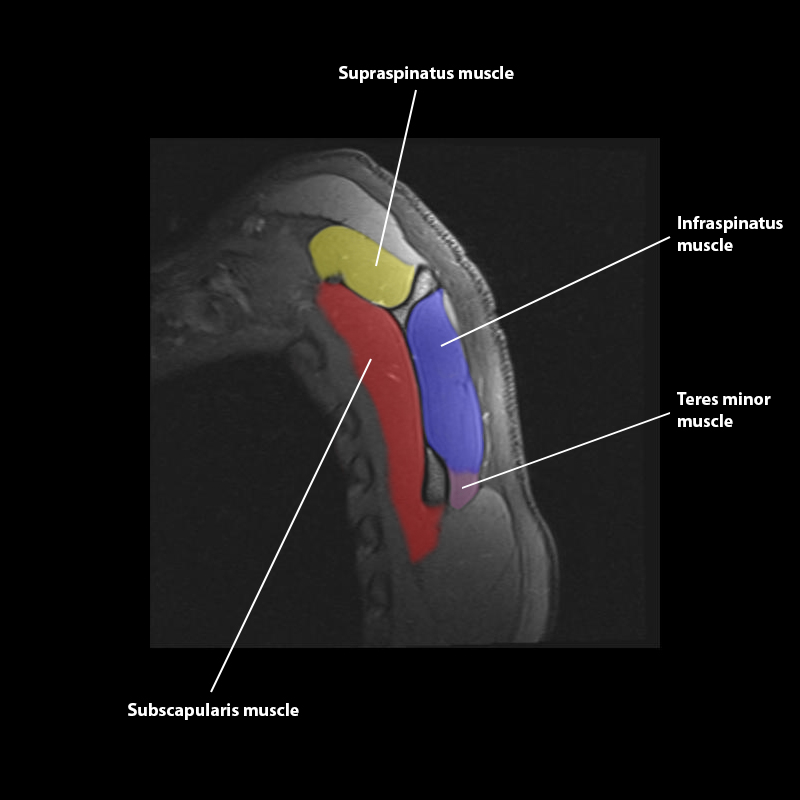

Shoulder MRI Anatomy